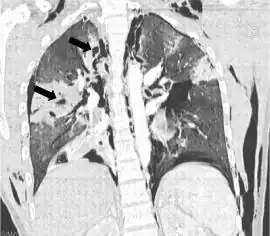

| Coronal CT scan showing lucencies (pale areas in radiography) in the lung caused by pulmonary lacerations on the left of the image (black arrows) | |

A pulmonary laceration is a chest injury in which lung tissue is torn or cut.[1] An injury that is potentially more serious than pulmonary contusion, pulmonary laceration involves disruption of the architecture of the lung,[2] while pulmonary contusion does not.[3] Pulmonary laceration is commonly caused by penetrating trauma but may also result from forces involved in blunt trauma such as shear stress. A cavity filled with blood, air, or both can form.[2] The injury is diagnosed when collections of air or fluid are found on a CT scan of the chest. Surgery may be required to stitch the laceration, to drain blood, or even to remove injured parts of the lung. The injury commonly heals quickly with few problems if it is given proper treatment; however it may be associated with scarring of the lung or other complications.